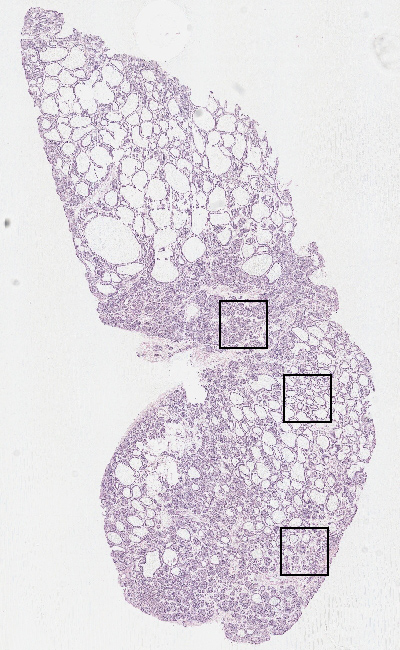

Glandular cells:

90

Other cell types:

10